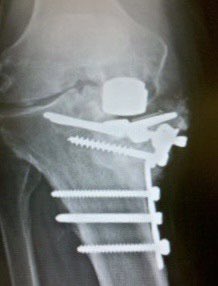

*I know it’s a Sigma RP but that DepuyTeflonTech™️ coating don’t lie